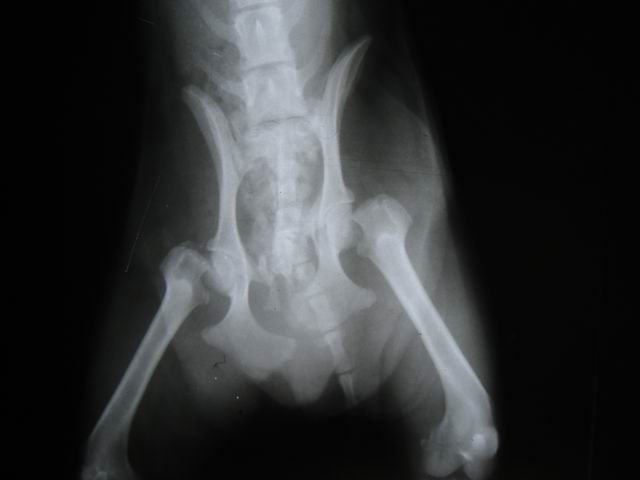

近有客户想要了解 下宠物X光机拍片的突显,以下使用我公司生产的宠物X光机拍摄的照片。 如果您需要采购宠物X光机。可以致电:0536-8322186或18953679166! 上一篇:上一篇:拍片机成像系统点片方案有哪些 下一篇:下一篇:如何区分CR拍片机和DR拍片机